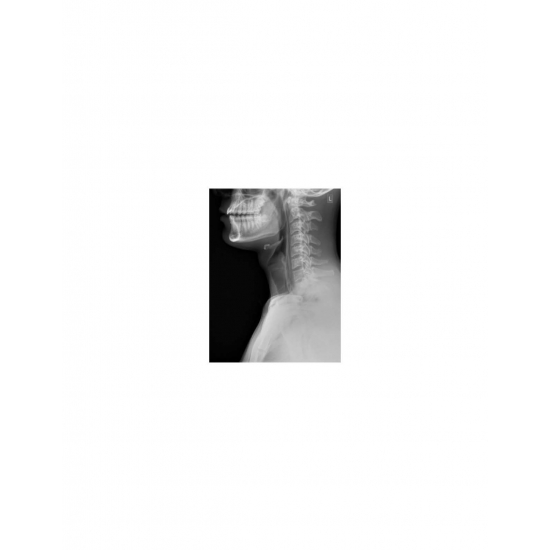

| Odynophagia In A Collegiate Baseball Player - Page #3 | |||